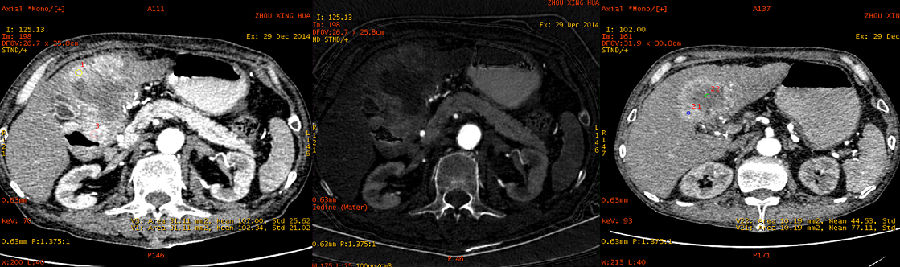

病灶内部密度不均,最大径线:7 × 11cm; GSI曲线分析:增厚的胃壁与外凸的部分能谱曲线一致,证明巨大病灶起源于胃; 延迟期观察,对比剂通过未受明显影响,胃壁无明显僵硬

实质期能谱曲线分析,显示病灶与腹腔内正常淋巴结曲线已有区别

胃恶性淋巴瘤 起自粘膜层,并向粘膜下层和肌层呈浸润性生长。病变可单发或多发,可局部侵犯,也可侵及全胃 临床上,该病最常需与浸润性胃癌鉴别 常规CT扫描可就病变的大小,范围,与邻近器官组织的关系作出判断,但往往缺乏有确诊价值的表现,尤其对生长巨大的病灶,其起源和与邻近结构的关系很难作出准确分析,无法明确地鉴别浸润性胃癌,仅能结合消化道造影对该病作出估计性的诊断,该病实为常规CT诊断难点之一 能谱CT扫描GSI能谱曲线分析及基物质图像分析可对病灶的起源,与向外生长部分同源性的判定,强化程度,相关淋巴结是否同源受侵等做出较准确判断,有助提高该病CT诊断准确率。如本例,通过同源性分析,明确排除了肝脏原发病灶,明确了胃及十二指肠区巨大病灶均起源于胃,通过碘基图像,发现强化程度不及正常肝脏及胃壁,通过多期相GSI图像分析,明确了对比剂通过未受明显影响,胃尚有蠕动;综合上述征象,可比较有把握地作出胃恶性淋巴瘤的诊断。